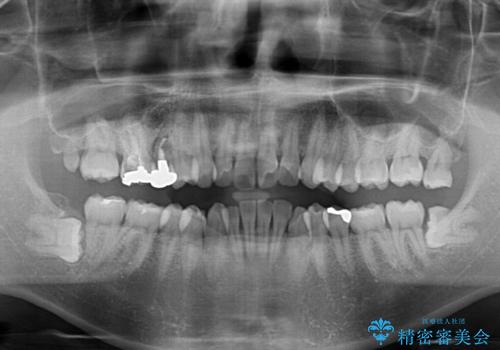

レントゲン撮影により、右上奥歯が折れていることが分かりました。

患者様自身も何となく違和感を覚えていたとのことで、インプラント補綴治療を行うこととしました。

歯列不正は比較的軽微であったので、インビザラインによる矯正治療とし、矯正治療中にタイミングを見て抜歯とインプラント埋入を行う予定としました。

破折して抜歯が必要となった歯の後ろの歯は、根管治療が必要な状態であったので、根管治療を行い、矯正治療後にインプラント部の補綴治療と同時にセラミッククラウンを装着しました。